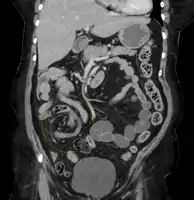

| Coronal CT of the abdomen, demonstrating a volvulus as indicated by twisting of the bowel stock | |